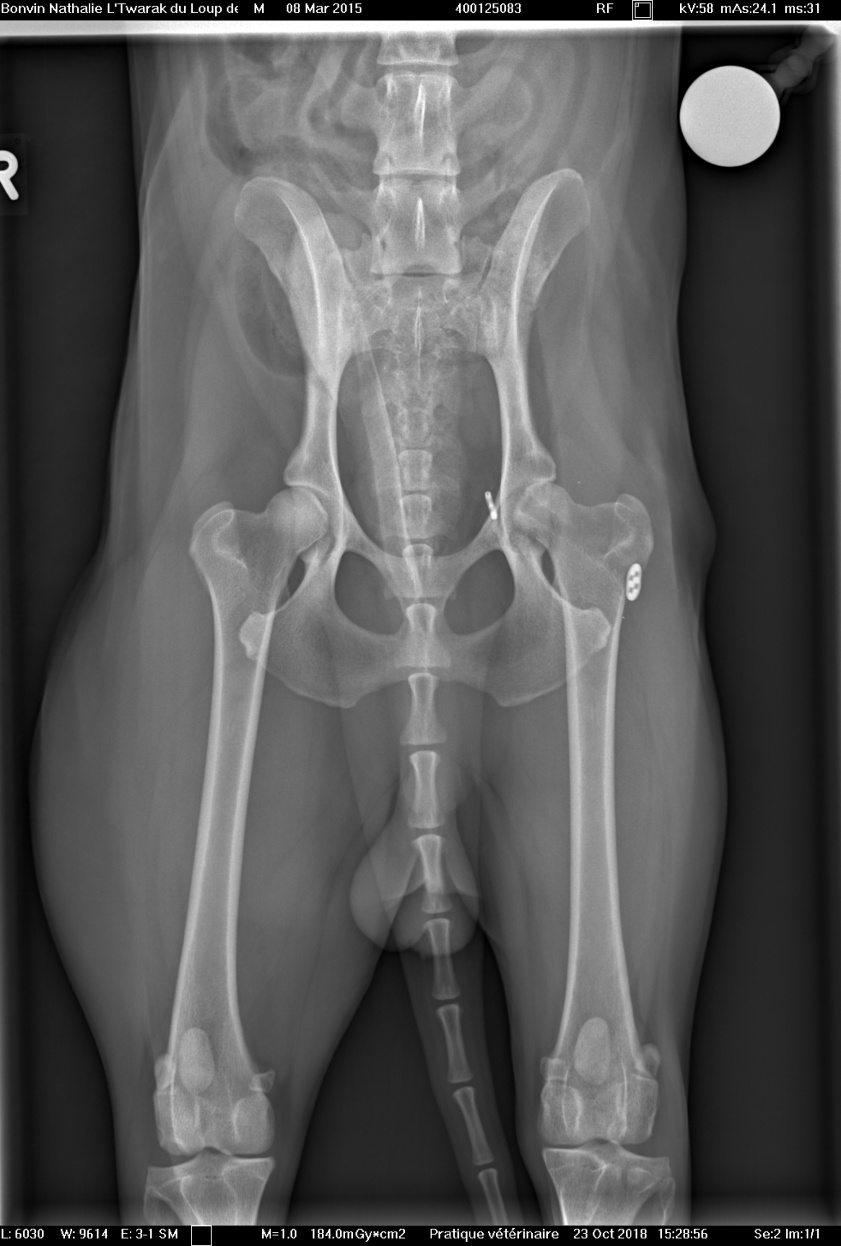

Voici les radios du 23 octobre... la tête du fémur est nécrosée...sur problème infectieux... je ne suis pas contente... la seule alternative qu'il reste maintenant et de tout enlever, de couper la tête du fémur... et Twarak devra vivre ainsi.

Il me dise que pour un chien comme lui, c'est très gérable... je suis triste pour Twarak....

opération et mise en place d'un bouton-clou dans la tête du fémur gauche